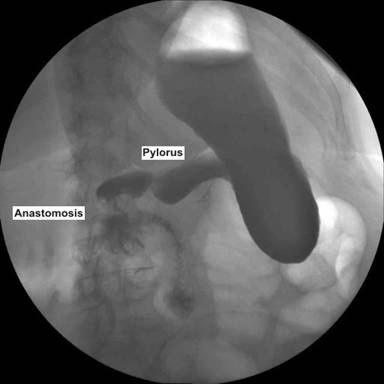

The patient started oral intake on the 3rd postoperative day following a swallow control (Figure 7). Recovery was uneventful and she was discharged on the 7th postoperative day. Upper digestive endoscopy performed three months after surgery showed a normal anastomosis.

Figure 7. Postoperative swallow control. |